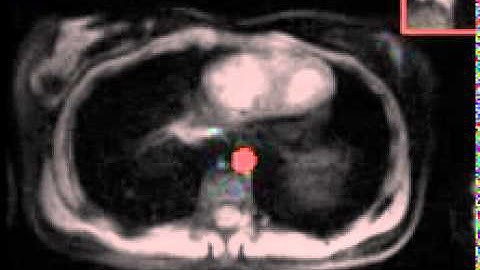

cardiac MRI Segmentation- Active Contour in MATLAB #shorts #matlab